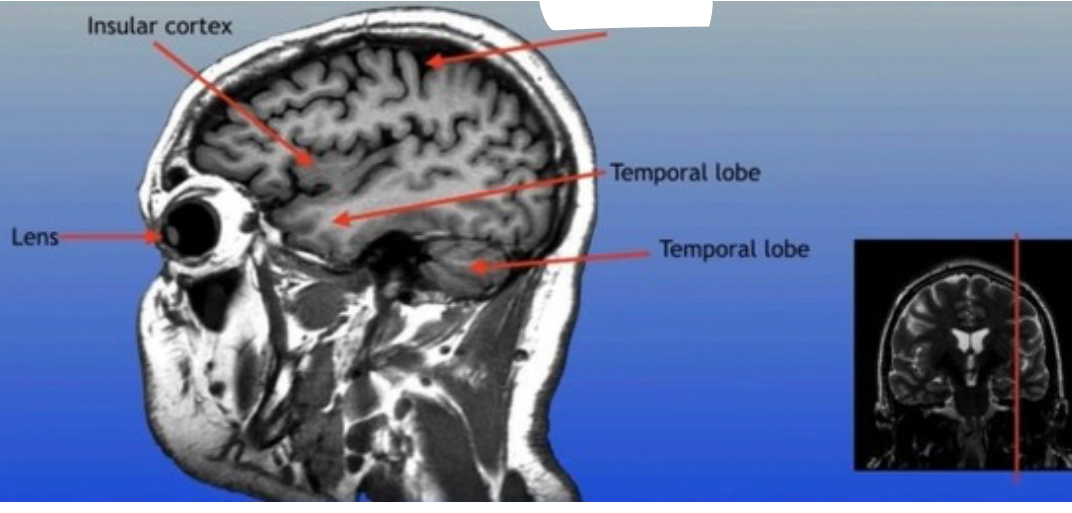

Insular Cortex

Region of the brain located deep within the lateral sulcus, involved in functions such as emotion processing and self-awareness.

Frontal Sinus

A paired cavity located within the frontal bone, above the eyes, that plays a role in sinus drainage and resonance of the voice.

Optic Nerve

The bundle of nerve fibers that transmits visual information from the retina to the brain. It plays a crucial role in the sense of sight.